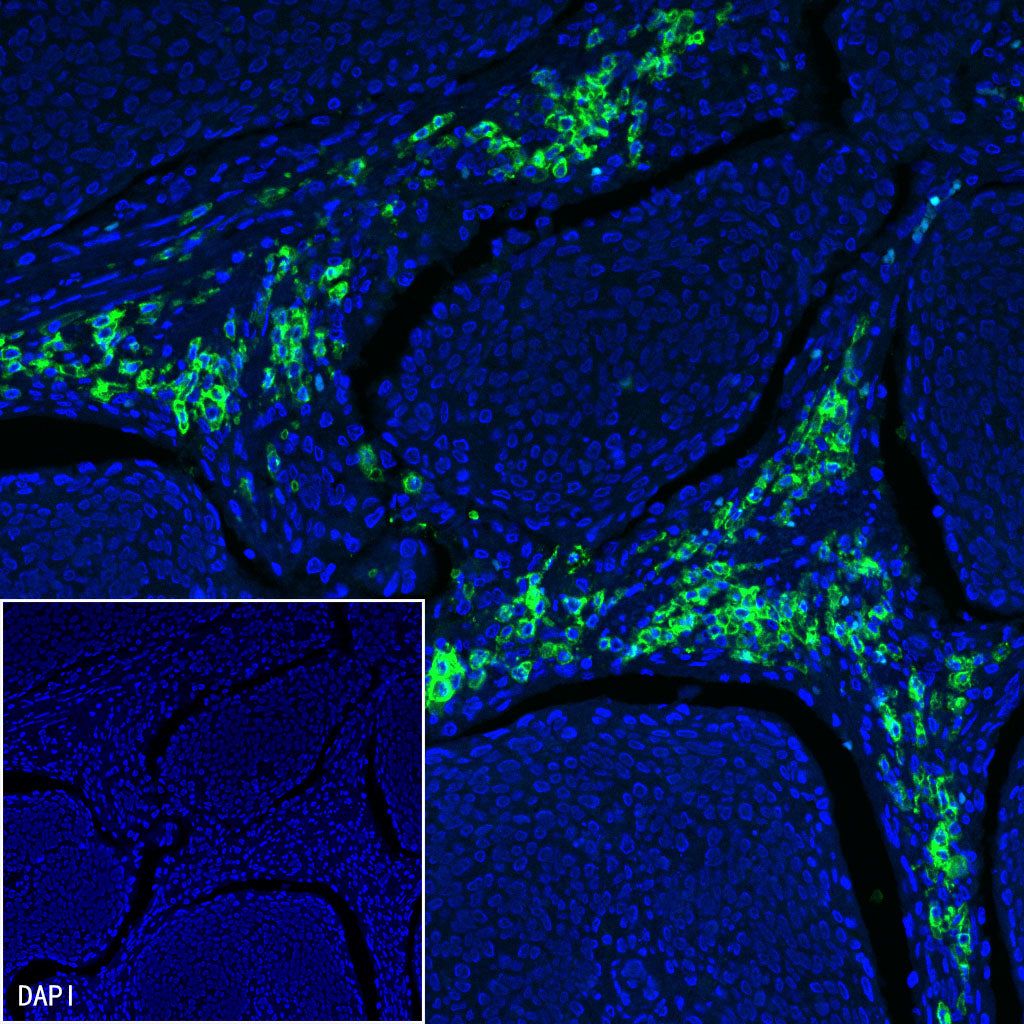

Immunofluorescence

IF shows positive staining in paraffin-embedded human cervical squamous cell carcinoma. Anti-CD38 antibody was used at 1/500 dilution (Green) and incubated overnight at 4°C. Goat polyclonal Antibody to Mouse IgG - H&L (Alexa Fluor® 488) (S0B4017) was used as secondary antibody at 1/500 dilution. Counterstained with DAPI (Blue). Heat mediated antigen retrieval with EDTA buffer pH9.0 was performed before commencing with IF staining protocol.